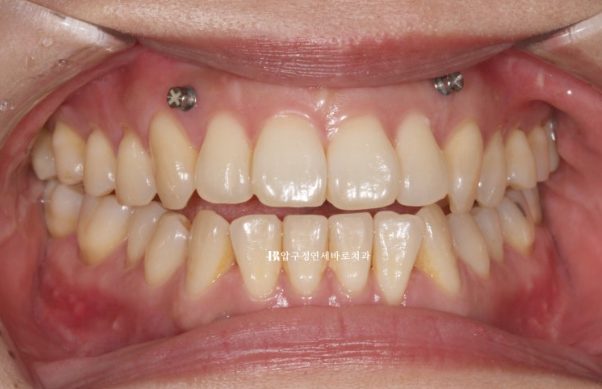

23.05

약 3개월 간 물리치료 후 내원했을 때 개방교합이 많이 줄어들었습니다.

여전히 남아있는 개방교합은 이제 교정으로 해결해야합니다.

이 상태에서 인비절라인 스캔도 하고 장치 제작에 들어갑니다.

장치제작과 배송에 걸리는 기간 한 달 반을 기다려서 첫 장치를 끼기 시작한 것은 23년 6월입니다.